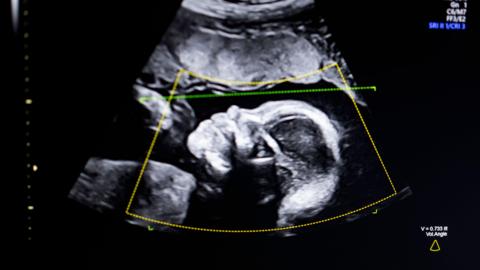

Some high-street clinics are putting lives at risk by allowing unqualified non-specialists to carry out baby scans, the Society of Radiographers (SoR) has warned.

It is concerned that anyone using an ultrasound machine can call themselves a sonographer and offer the service - often sold as a reassurance, souvenir or sexing scan - ahead of the routine 20-week NHS check.

Private clinics often offer reassurance or sexing scans before the standard NHS anomaly scan which is normally offered between 18 and 21 weeks into the pregnancy